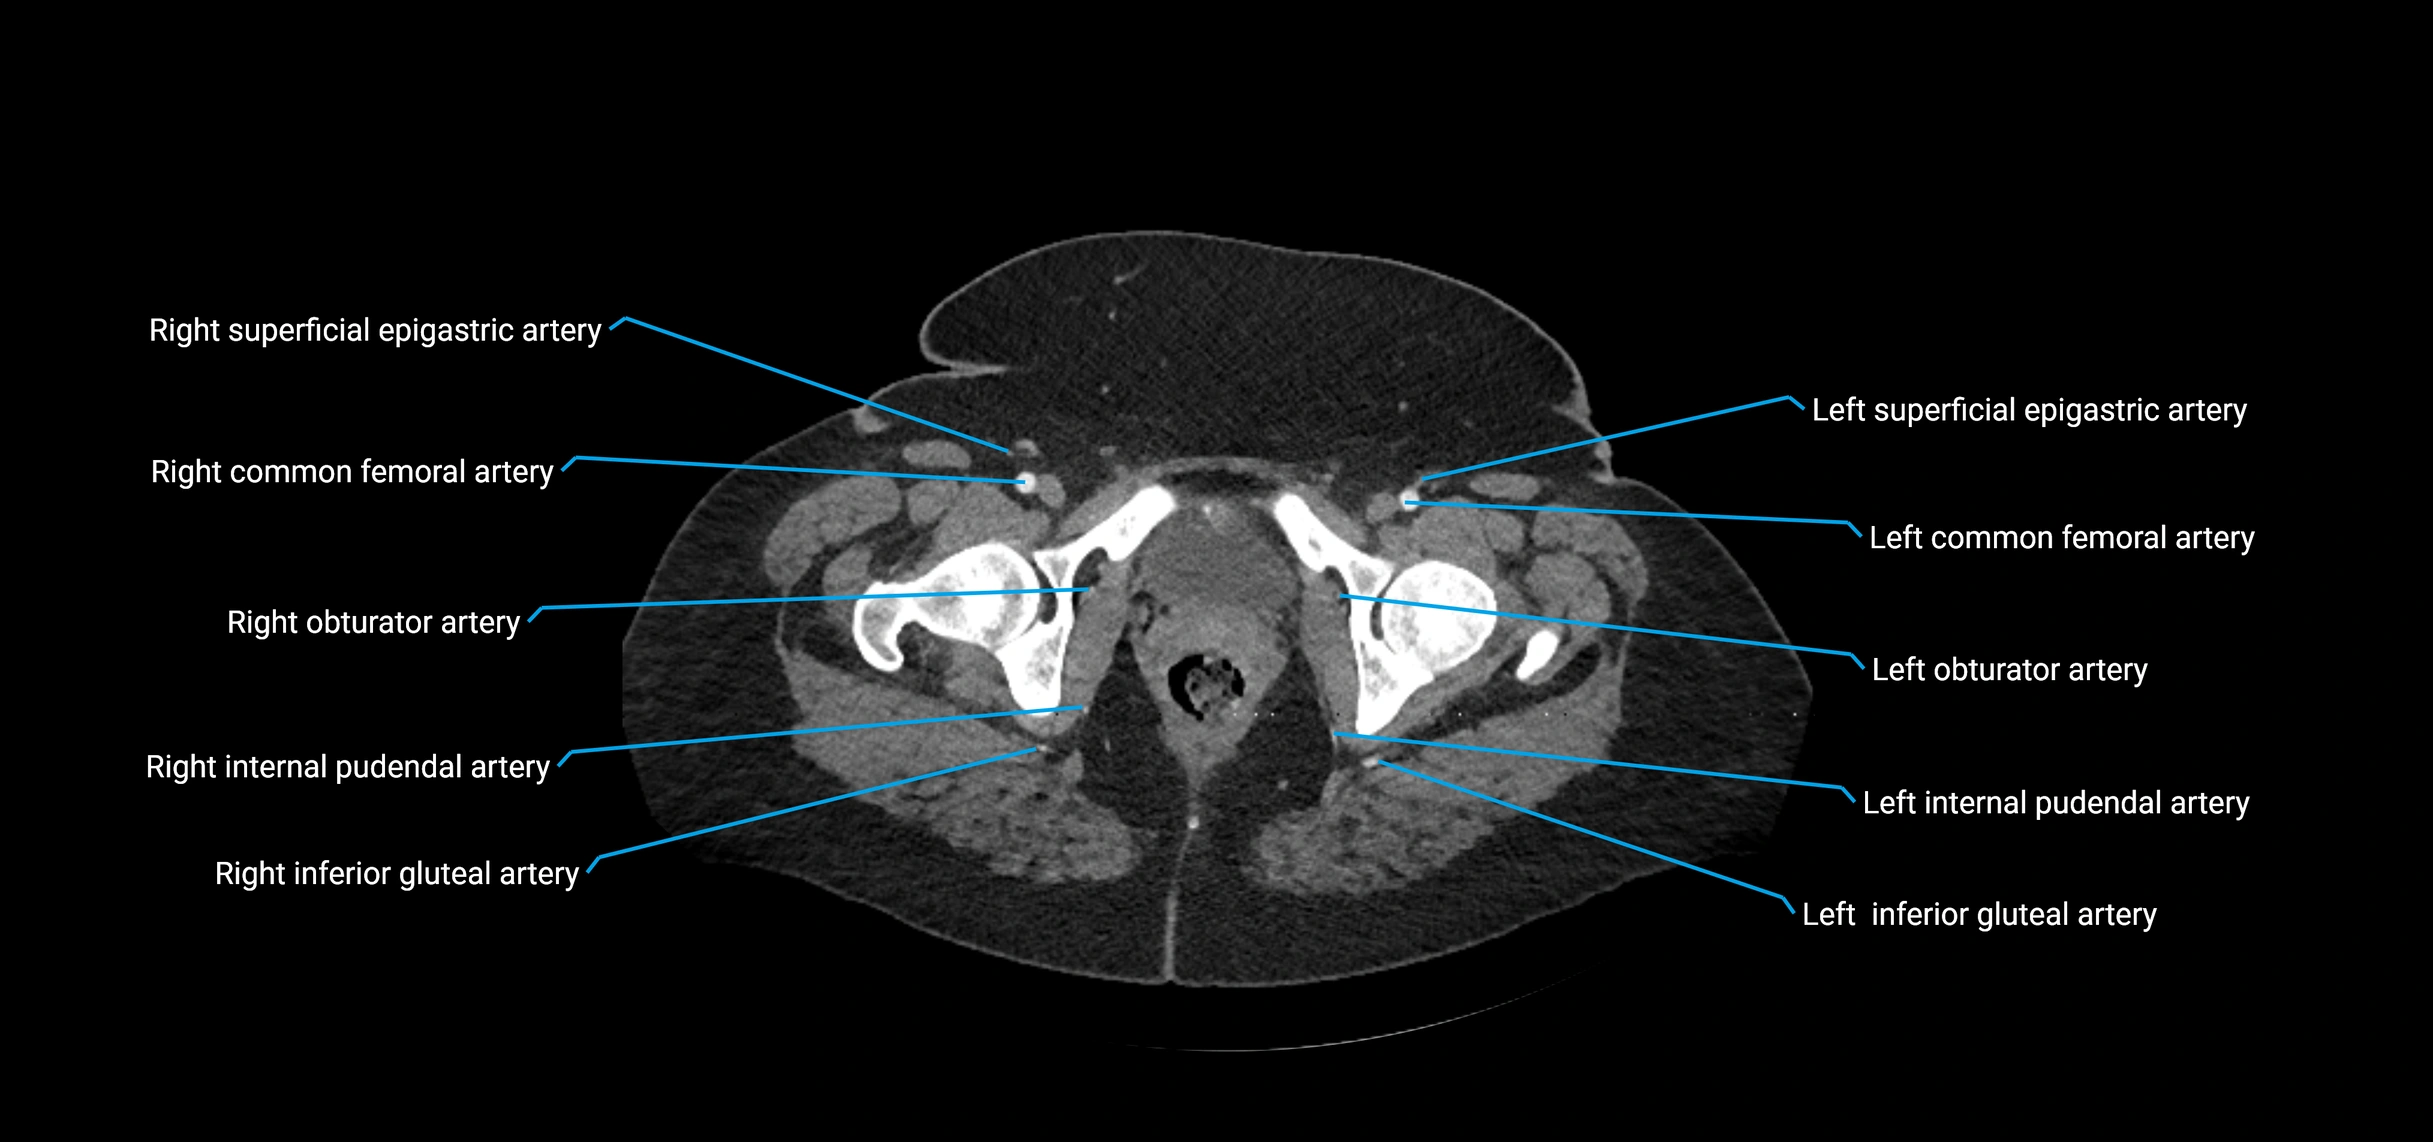

CT Appearance

Non-contrast CT:

• Appears as a tubular soft tissue structure anterior to vertebral bodies

• Calcified atherosclerotic plaques appear as hyperdense foci along the wall

• Useful for screening abdominal aortic aneurysm (AAA) size and mural calcification

Contrast-enhanced CT (CTA):

• Gold standard for abdominal aortic imaging

• Provides excellent detail of lumen, wall, aneurysm, thrombus, and branch vessels

• Multiplanar and 3D reconstructions help in aneurysm measurement, stent graft planning, and dissection evaluation

• Detects acute rupture, traumatic injury, or occlusion with high sensitivity

CT images

image